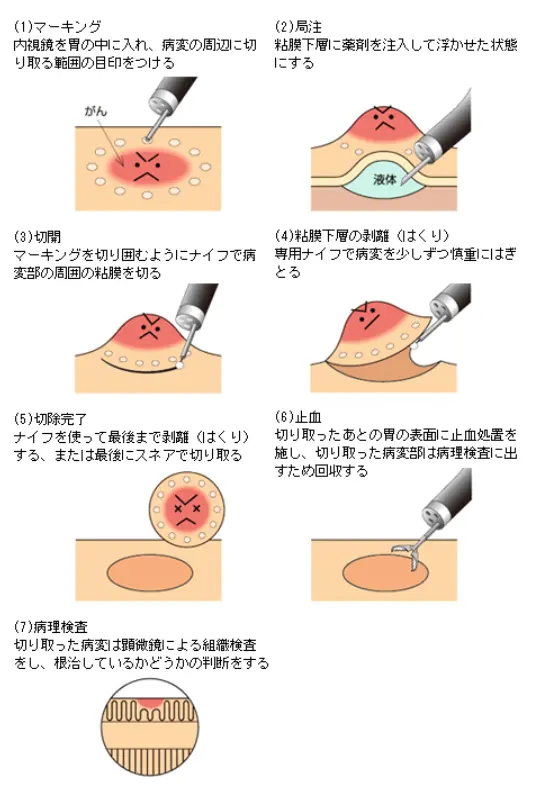

<ESDの手順>

食道・胃・十二指腸・大腸の早期がん、腺腫などを対象とする内視鏡治療です。ポリペクトミー、EMRでは切除困難な大きな病変であっても、ESDでは治療が可能です。おなかを切る必要がなく、外科手術と比べ体への負担が軽いのが最大の利点です。

術後の痛みは基本的にほとんどなく、デスクワークであれば退院の翌日から復帰出来ます。

ESD (内視鏡的粘膜下層剥離術)

長所:大きな病変でも切除出来る。

短所:入院が必要。

入院期間は食道・胃・大腸は5日間、十二指腸は7日間が目安です。